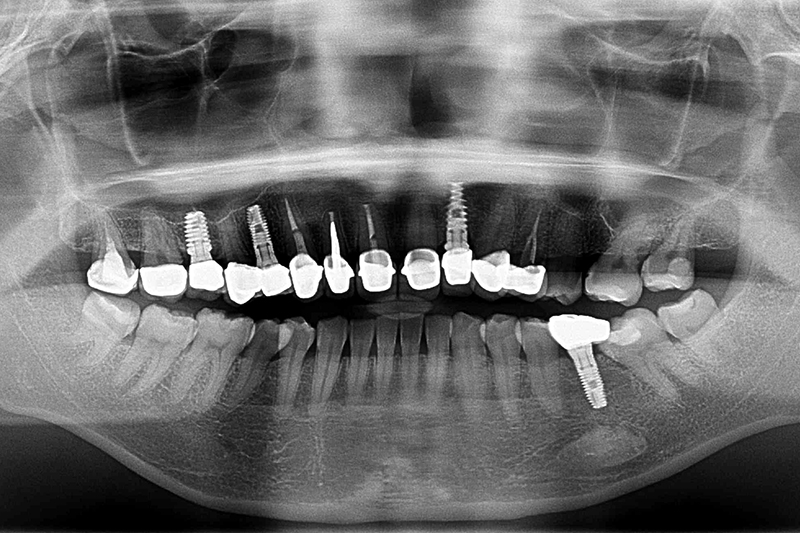

缺牙多顆-全口X光攝影

案例一

術前

術後